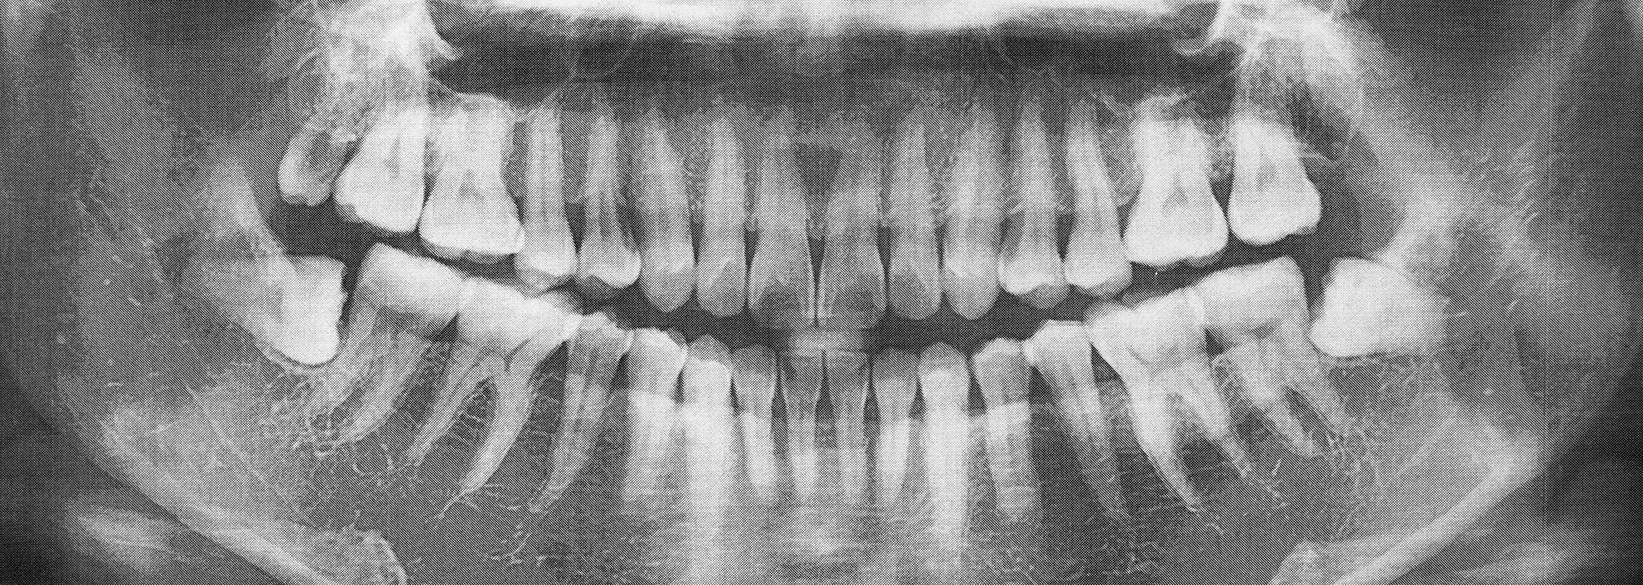

- Precise Treatment Planning with Advanced Imaging

The process of removing wisdom teeth can be fairly straightforward. We’ll either perform a simple or surgical procedure. If the teeth are visible above the gumline (partially erupted), we can use special instruments to gently loosen them until they detach from the connective tissues. If the molars are beneath the gumline (impacted), a surgical approach must be taken. A small incision is created in the gums so that each tooth can be removed swiftly and successfully.